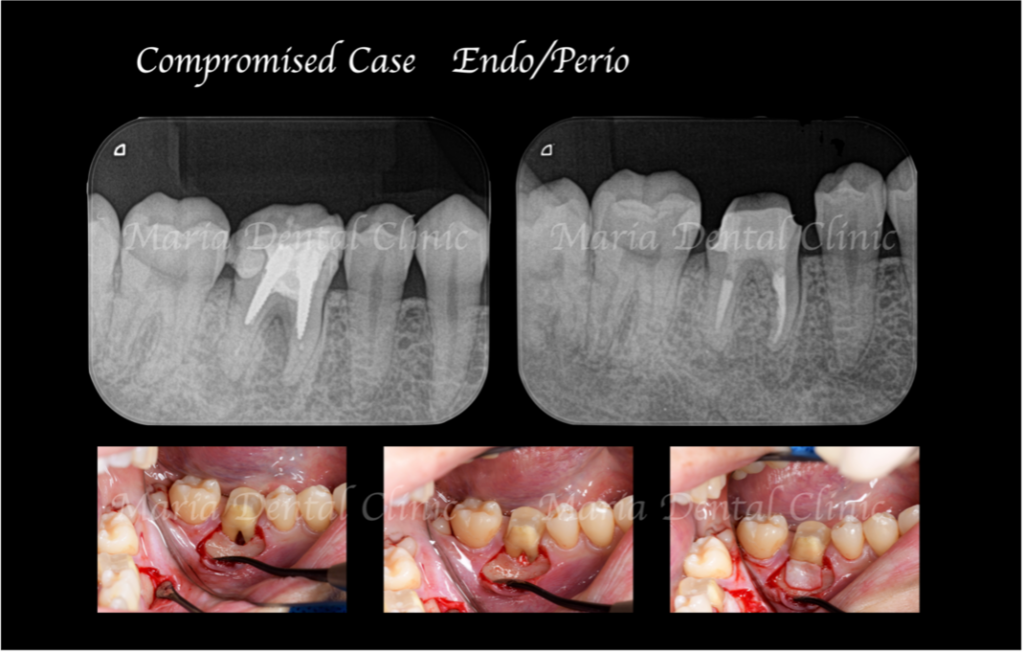

通法通り根管治療を施したことで歯ぐきの腫脹は改善したものの、分岐部(歯の股の部分)の歯周病に治癒傾向は確認されず(写真1術前)歯周病の治療に移行する判断をしました。

歯周病専門医による組織再生療法を行なった際にはレントゲンで透過像(黒い影)があった歯の股の部分の骨は著しく欠損していました(写真2術中)。骨の欠損部分に組織再生治療を行い、さらに3ヶ月の経過観察を行い生体の治癒を待ちました。

歯周組織再生療法3ヶ月後には分岐部(歯の股の部分)に確認されていた歯周病(術前写真)は完全に治癒していることを確認しました(術後3か月写真)。また同時に、術前に確認できた根尖性歯周炎も綺麗な治癒が確認できたことから最終補綴処置へ移行しました。今後最低2年間は歯肉、根尖周囲組織の治癒経過を患者様にご協力いただき確認していく予定です。